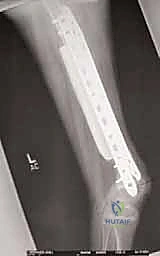

"First, we gather all our intelligence. This involves a multi-modality imaging approach. We start with plain radiographs – AP and lateral views are crucial. Look closely at the bone geometry, the exact size of the lesion, and critically, the remaining host bone stock. We need to assess its quality and quantity to ensure it can adequately support our planned reconstruction, whether it's an allograft or an endoprosthesis. Remember, inadequate bone stock means we must convert to a joint-replacing reconstruction, so this assessment is non-negotiable. Radiographs also give us our initial templating parameters for allograft sizing.

Here we see a preoperative AP radiograph, clearly delineating a diaphyseal lesion in the femur. This is our starting point for understanding the extent of bone involvement.